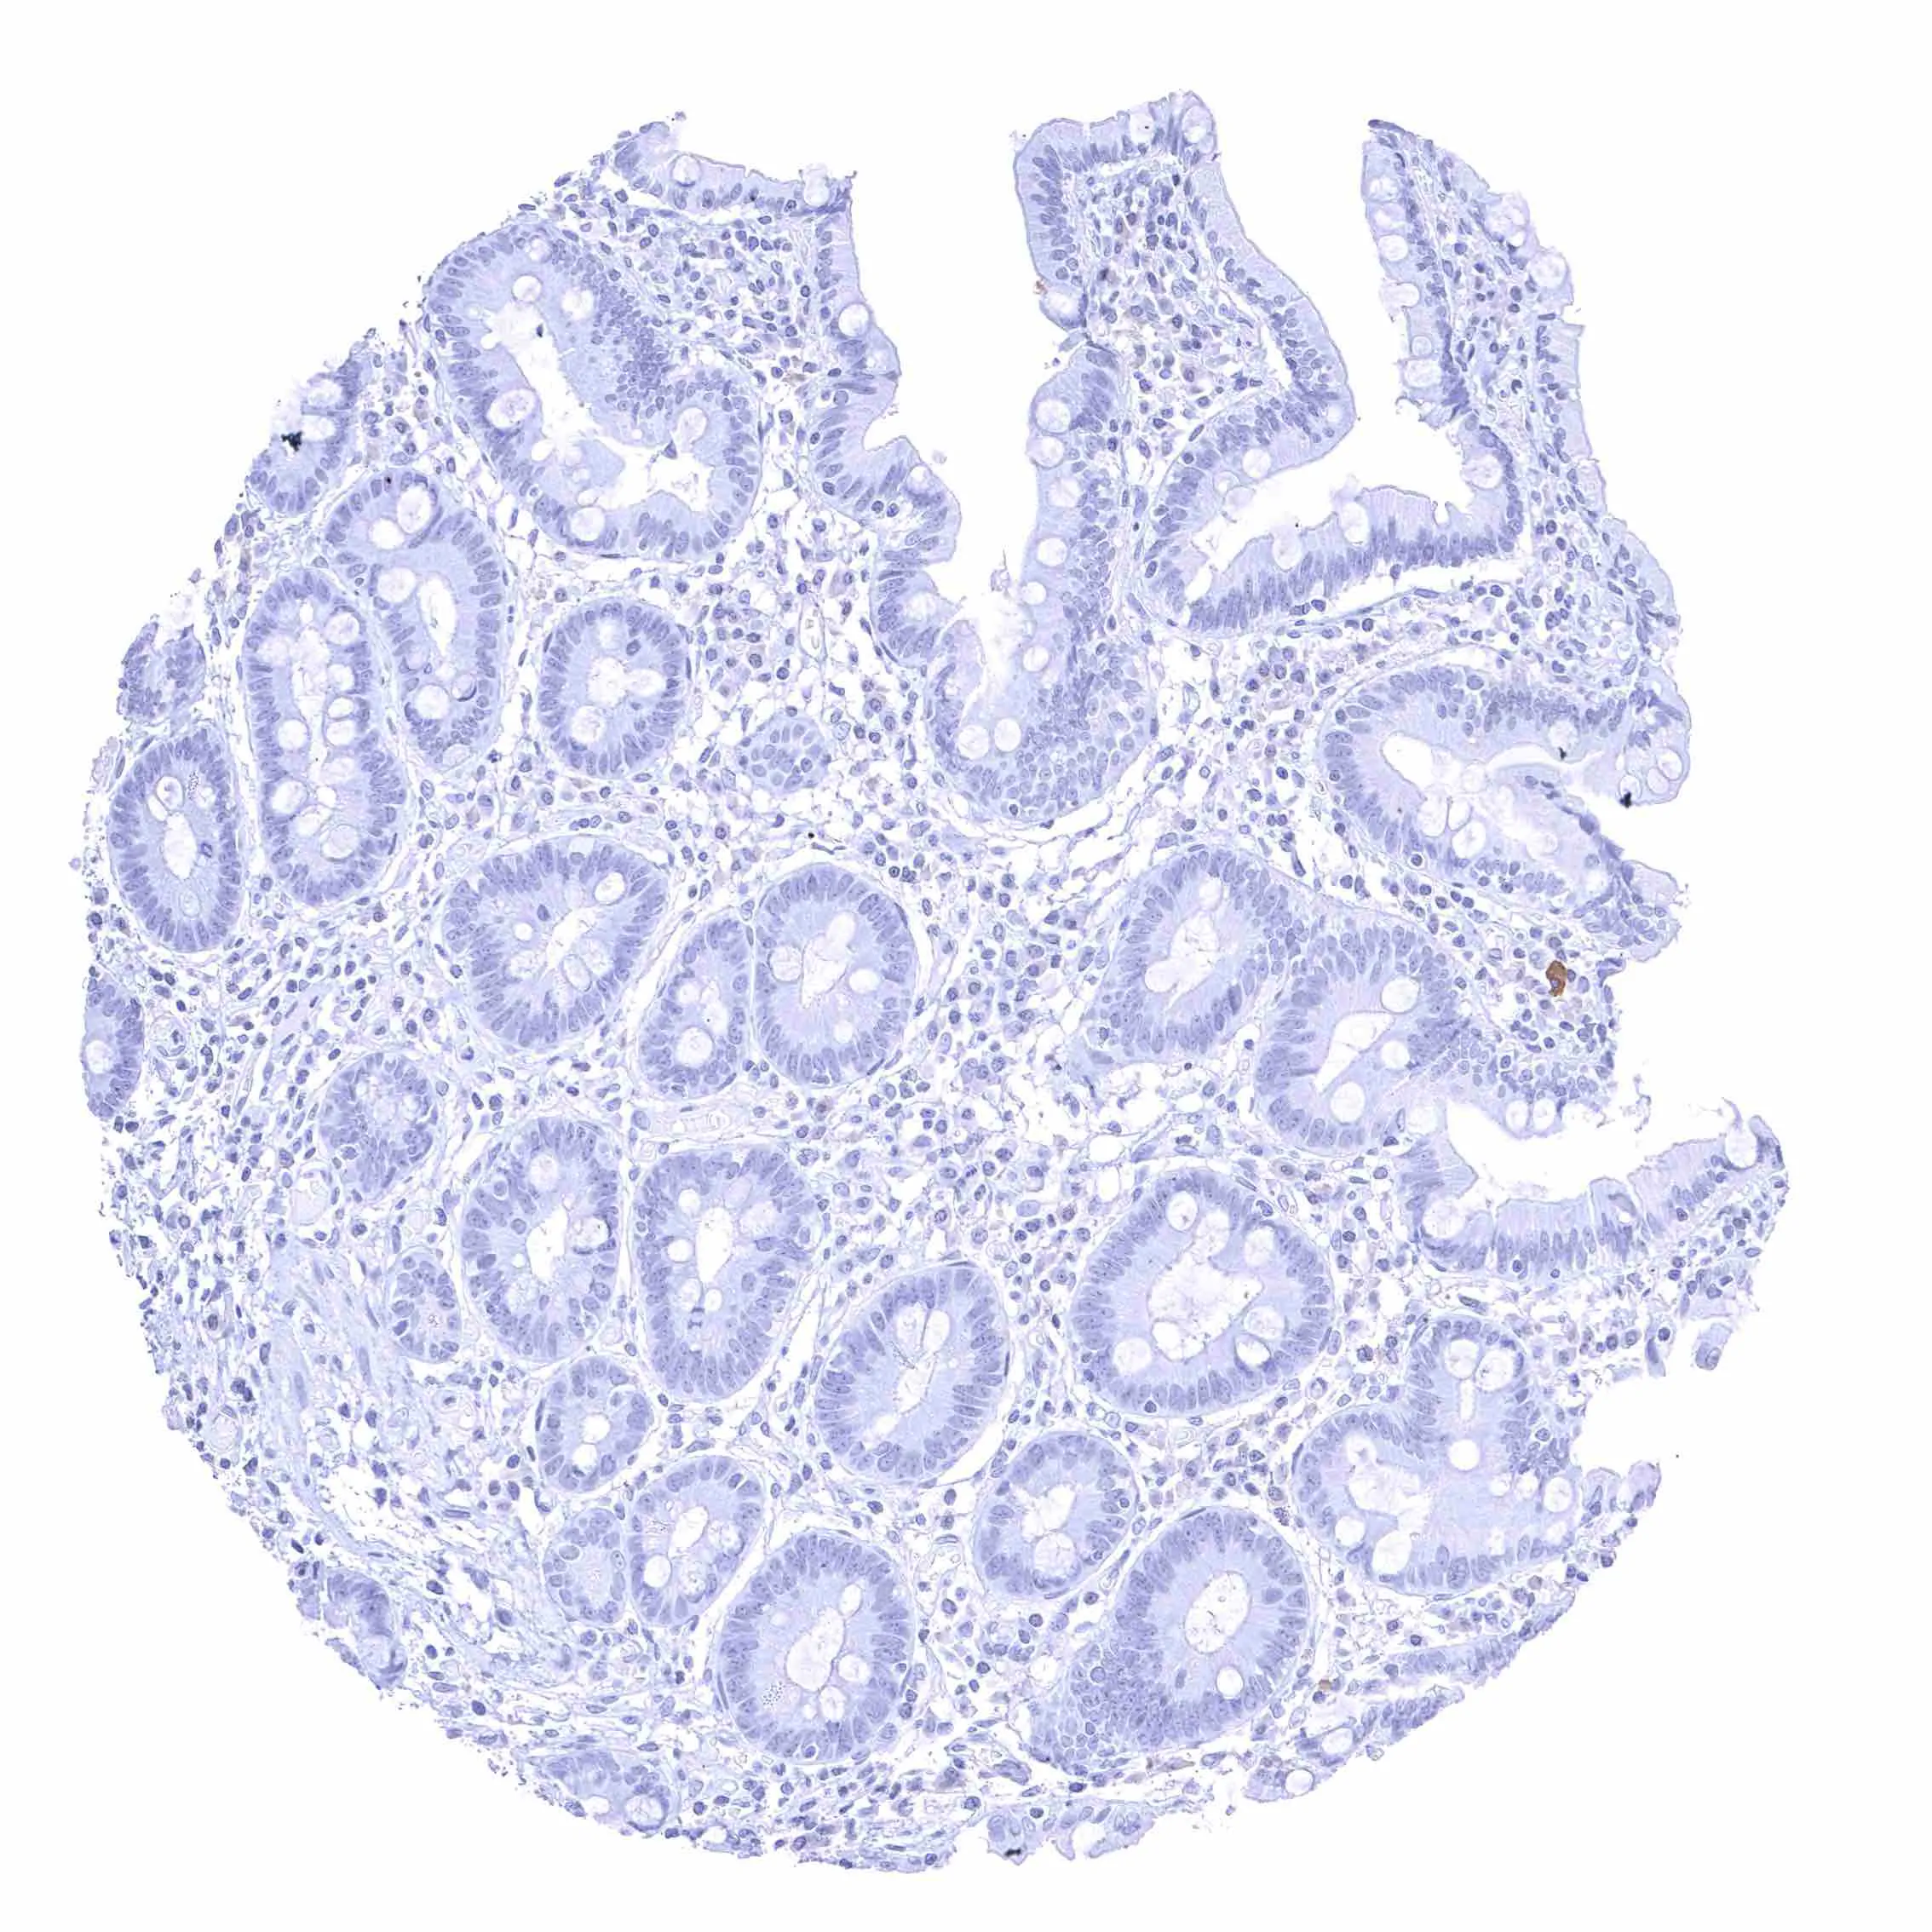

Appendix, mucosa